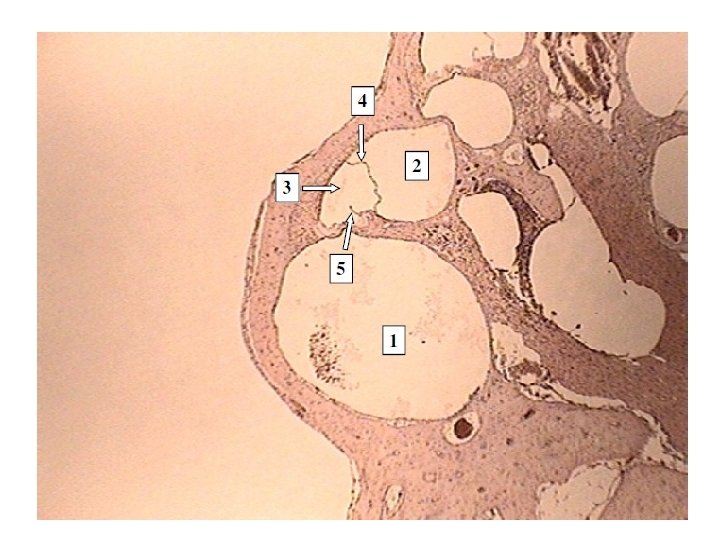

Sectional View of the Cochlear as it will appear on a microscope slide

Internal Anatomy of the Cochlea with details of the Bony Labyrinth